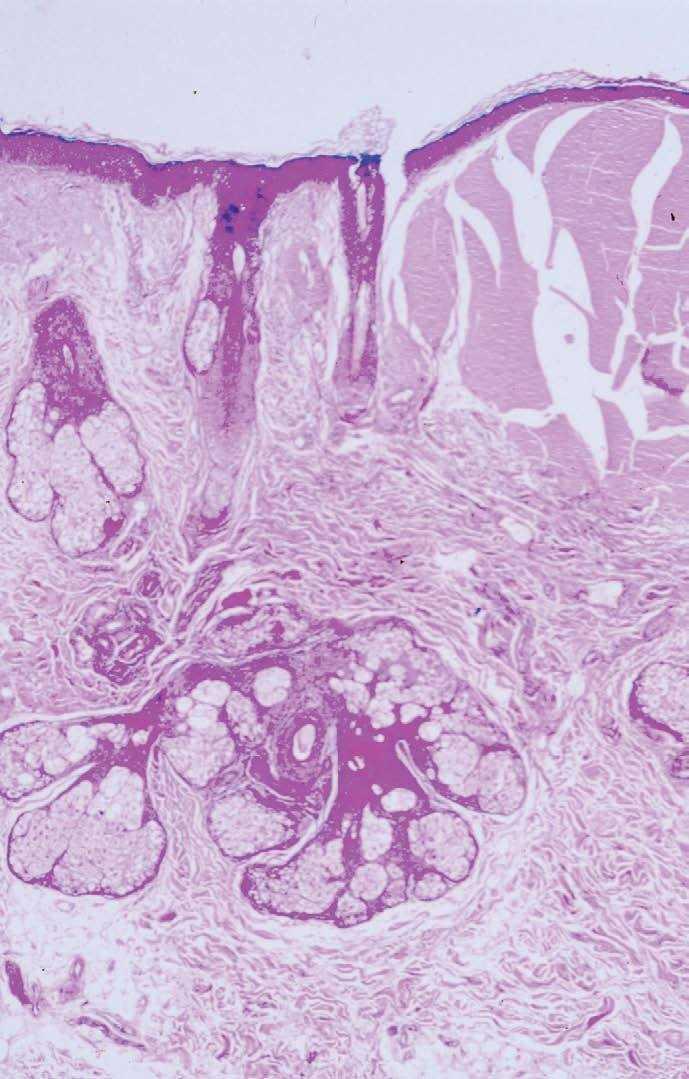

Fig. 4.--Masa eosinofílica fisurada, rodeada por un collarete acantótico y restos celulares en su interior. Delgada banda grenz que separa la zona de la membrana basal del depósito coloide. (Hematoxilina-eosina, x200.)